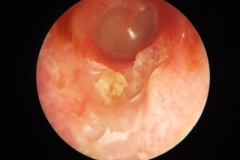

Cholesteatoma Clinical